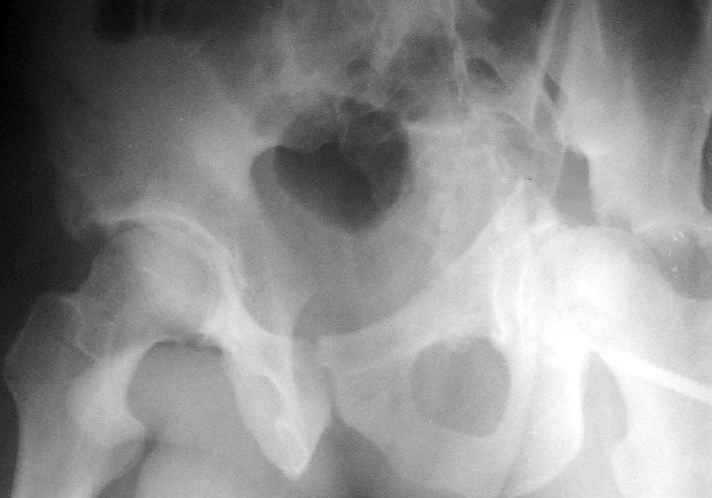

Пациент переведен в нашу клинику на 5 день после множественной травмы 25.01.2003 - двустороннее повреждение вертлужных впадин, разрыв левого крестцово-подвздошного сочленения. Вывихи обоих бедер. В месте первичного поступления подвздошный вывих правого бедра вправлен 26.01.2003, наложено вытяжение за левую вертельную область. Остеосинтез левой вертлужной впадины выполнен у нас 6.02.2003. Вопрос: надо ли синтезировать задне-верхний край правой вертлужной впадины?

впадины. Такое впечатление что на КТ есть интерпозиция кусочком, тогда уж точно надо туда залесть, а так, я считаю не стоит.

Уважаемый Алексей, через месяц после повреждения обострять травму, чтобы продлить "колясочный" срок? Второй сустав станет опорным не скоро.Головка на Ртг концентрически вставлена, задний фрагмент не интерпонирует, лимбус,по видимому тоже, ямочный фрагмент мешать не должен,герметизирующую манжету адекватно восстановить, обычно, не удается. Выгоды от оперативного вмешательства сомнительны. Я бы оперировать не стал.Еще месяц без нагрузки (по меньшей мере) и в нашей "конторе"- МОНИКИ(Вы наверняка знаете О.Ш.Буачидзе) положились бы на ощущения пациента при активных движениях правым бедром. Можно и сейчас проверить на возможность блокады и тогда принимать окончательное решение.